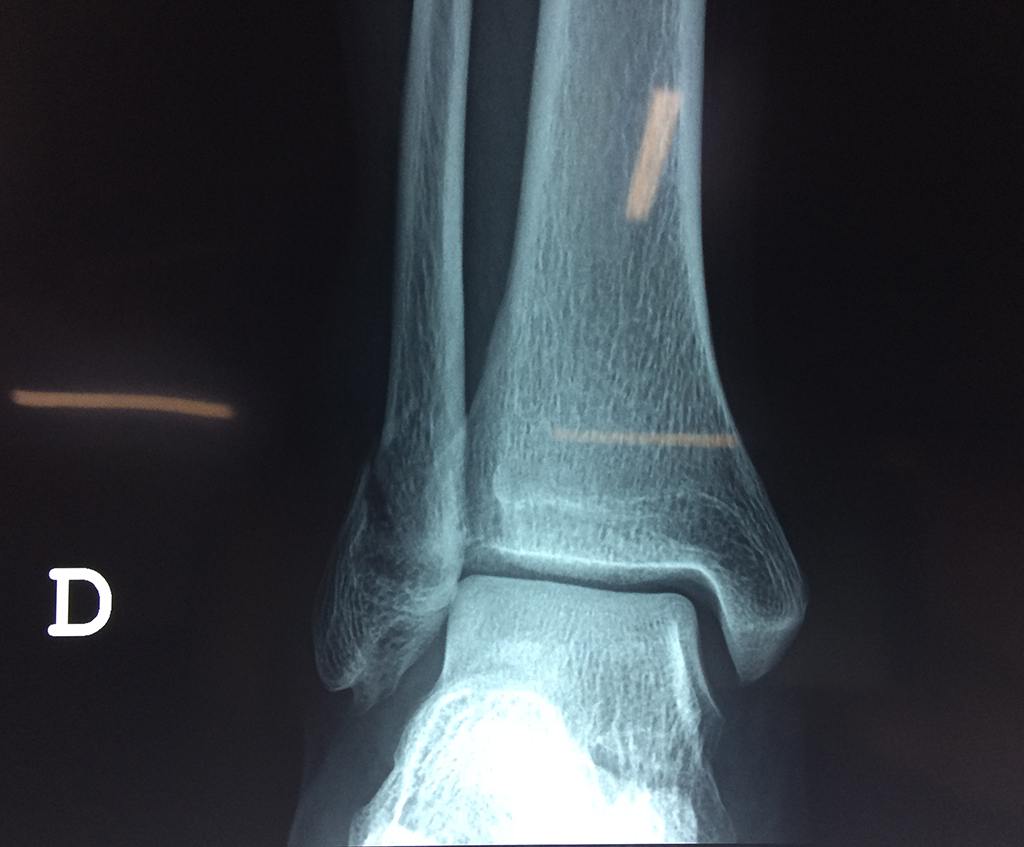

Una fractura de tobillo es la rotura de uno o más de los huesos del tobillo. Estas fracturas pueden ser:

- Parciales (el hueso está sólo parcialmente fisurado, no del todo).

- Completas (el hueso está perforado y está en 2 partes).

- Los extremos de los huesos están desalineados entre sí (desplazados).